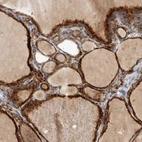

Immunohistochemical staining of human thyroid gland shows strong cytoplasmic positivity in glandular cells.